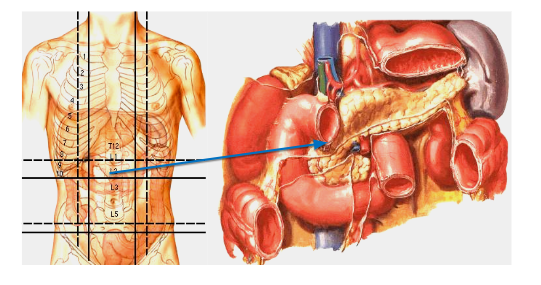

13. Giải phẫu ứng dụng

14. Sinh lý

Tụy:

- Nội tiết: Insulin, glucagon, sandostatin, polypeptid tụy

- Ngoại tiết: Amylase, lipase, trypsin, chymotrypsin, carboxypeptidase A & B

- Số lượng: 1500 – 2500 ml, pH 8 – 8,3

🡪 Ống tụy tổn thương 🡪 rò tụy

Tá tràng:

- Là hành lang nối dạ dày – hỗng tràng

- 10 lít dịch đi qua/24 giờ: Nước bọt 2l, dịch dạ dày 3l, mật 1l, tụy 2,5l

- Men tiêu đạm của tụy hoạt hoá nhờ enterokinase trong môi trường kiềm ở lòng tá tràng

🡪 Tổn thương khó liền, tỷ lệ bục và rò miệng nối cao